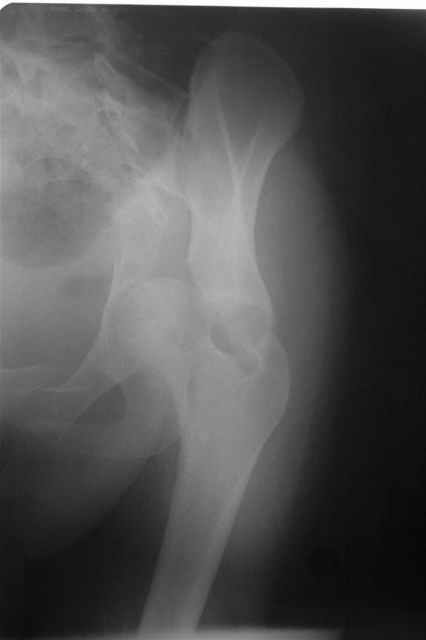

Трудности возникли сразу после рассечения большой ягодичной мыцы - короткие наружные ротаторы едва ли определялись - головка и шейка (как видно на

снимке) ушли в таз, пришлось воспользоваться дистрактором( ручные попытки выдернуть голову из под проксимального фрагмента - безуспешны) Шарнирный дистрактор - великое изобретение, без него репозиция была просто невозможна.

> Трудности возникли сразу после рассечения большой ягодичной мыцы - короткие

> наружные ротаторы едва ли определялись - головка и шейка

> ( как видно на

> снимке) ушли в таз, пришлось воспользоваться дистрактором

> ( ручные попытки выдернуть голову из под проксимального фрагмента - безуспешны)